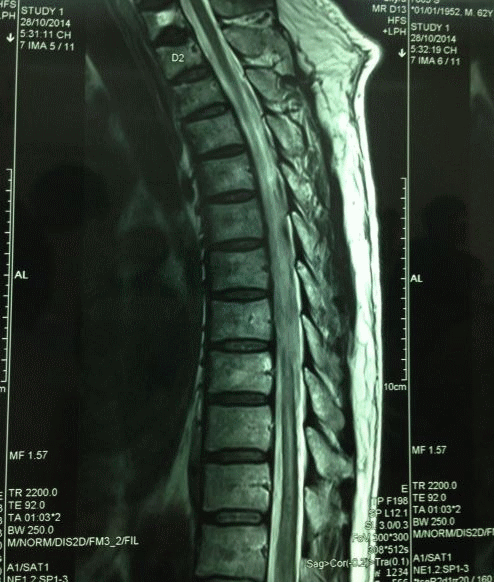

4. Đặc trưng hình ảnh nhồi máu tủy sống

Nhồi máu tủy sống là một chẩn đoán lâm sàng; tuy nhiên, hình ảnh có thể có ích để xác định chẩn đoán và loại trừ các khả năng khác. CT không có độ phân giải đủ để chẩn đoán nhồi máu tủy sống nhưng có thể có ích để loại trừ ép tủy do tụ máu ngoài màng cứng nếu MRI bị chống chỉ định.

MRI có thể thấy tăng tín hiệu trên T2 “giống bút chì” kéo dài trên các xung cắt đứng dọc do phù tủy độc tế bào. Tăng ngấm thuốc đối quang từ gadolinium thường không gặp trong giai đoạn cấp, và sự có mặt của dấu hiệu này sẽ đặt ra nghi vấn về các nguyên nhân khác. Teo tủy sống cuối cùng sẽ thay thế sưng phù trong pha mạn tính của bệnh.

Các biến đổi tín hiệu trên T2 có thể mất vài giờ đến vài ngày để bộc lộ, và độ nhạy do đó là thấp trong giai đoạn tối cấp. Trái lại, xung DWI có khả năng xác định được các biến đổi do thiếu máu cục bộ tối cấp trong tủy sống, nhưng độ nhạy là không hoàn hảo vì kích thước nhỏ của tủy sống và các nhiễu ảnh liên quan.

Độ nhạy chung đã được báo cáo của MRI trong chẩn đoán nhồi máu tủy sống khác nhau trong y văn, và sự khác nhau này có khả năng liên quan đến thời gian chụp từ khi khởi phát triệu chứng và độ nặng của bệnh (khả năng bắt được các bất thường hình ảnh tăng lên theo độ nặng của bệnh và khả năng thấy được biến đổi tín hiệu trên T2 tăng lên theo thời gian).

Hơn nữa, MRI có thể đưa ra các gợi ý về nguyên nhân của nhồi máu. Ví dụ, những bệnh nhân thuyên tắc mạch sụn xơ thường có bằng chứng của phình đĩa đệm tương ứng với vị trí có tổn thương tủy sống. Hình ảnh chụp mạch thường không được chỉ định trong nhồi máu tủy sống cấp tính trừ khi có nghi ngờ một rò động-tĩnh mạch màng cứng tủy sống hoặc một lóc tách động mạch chủ cấp chưa được xác định.